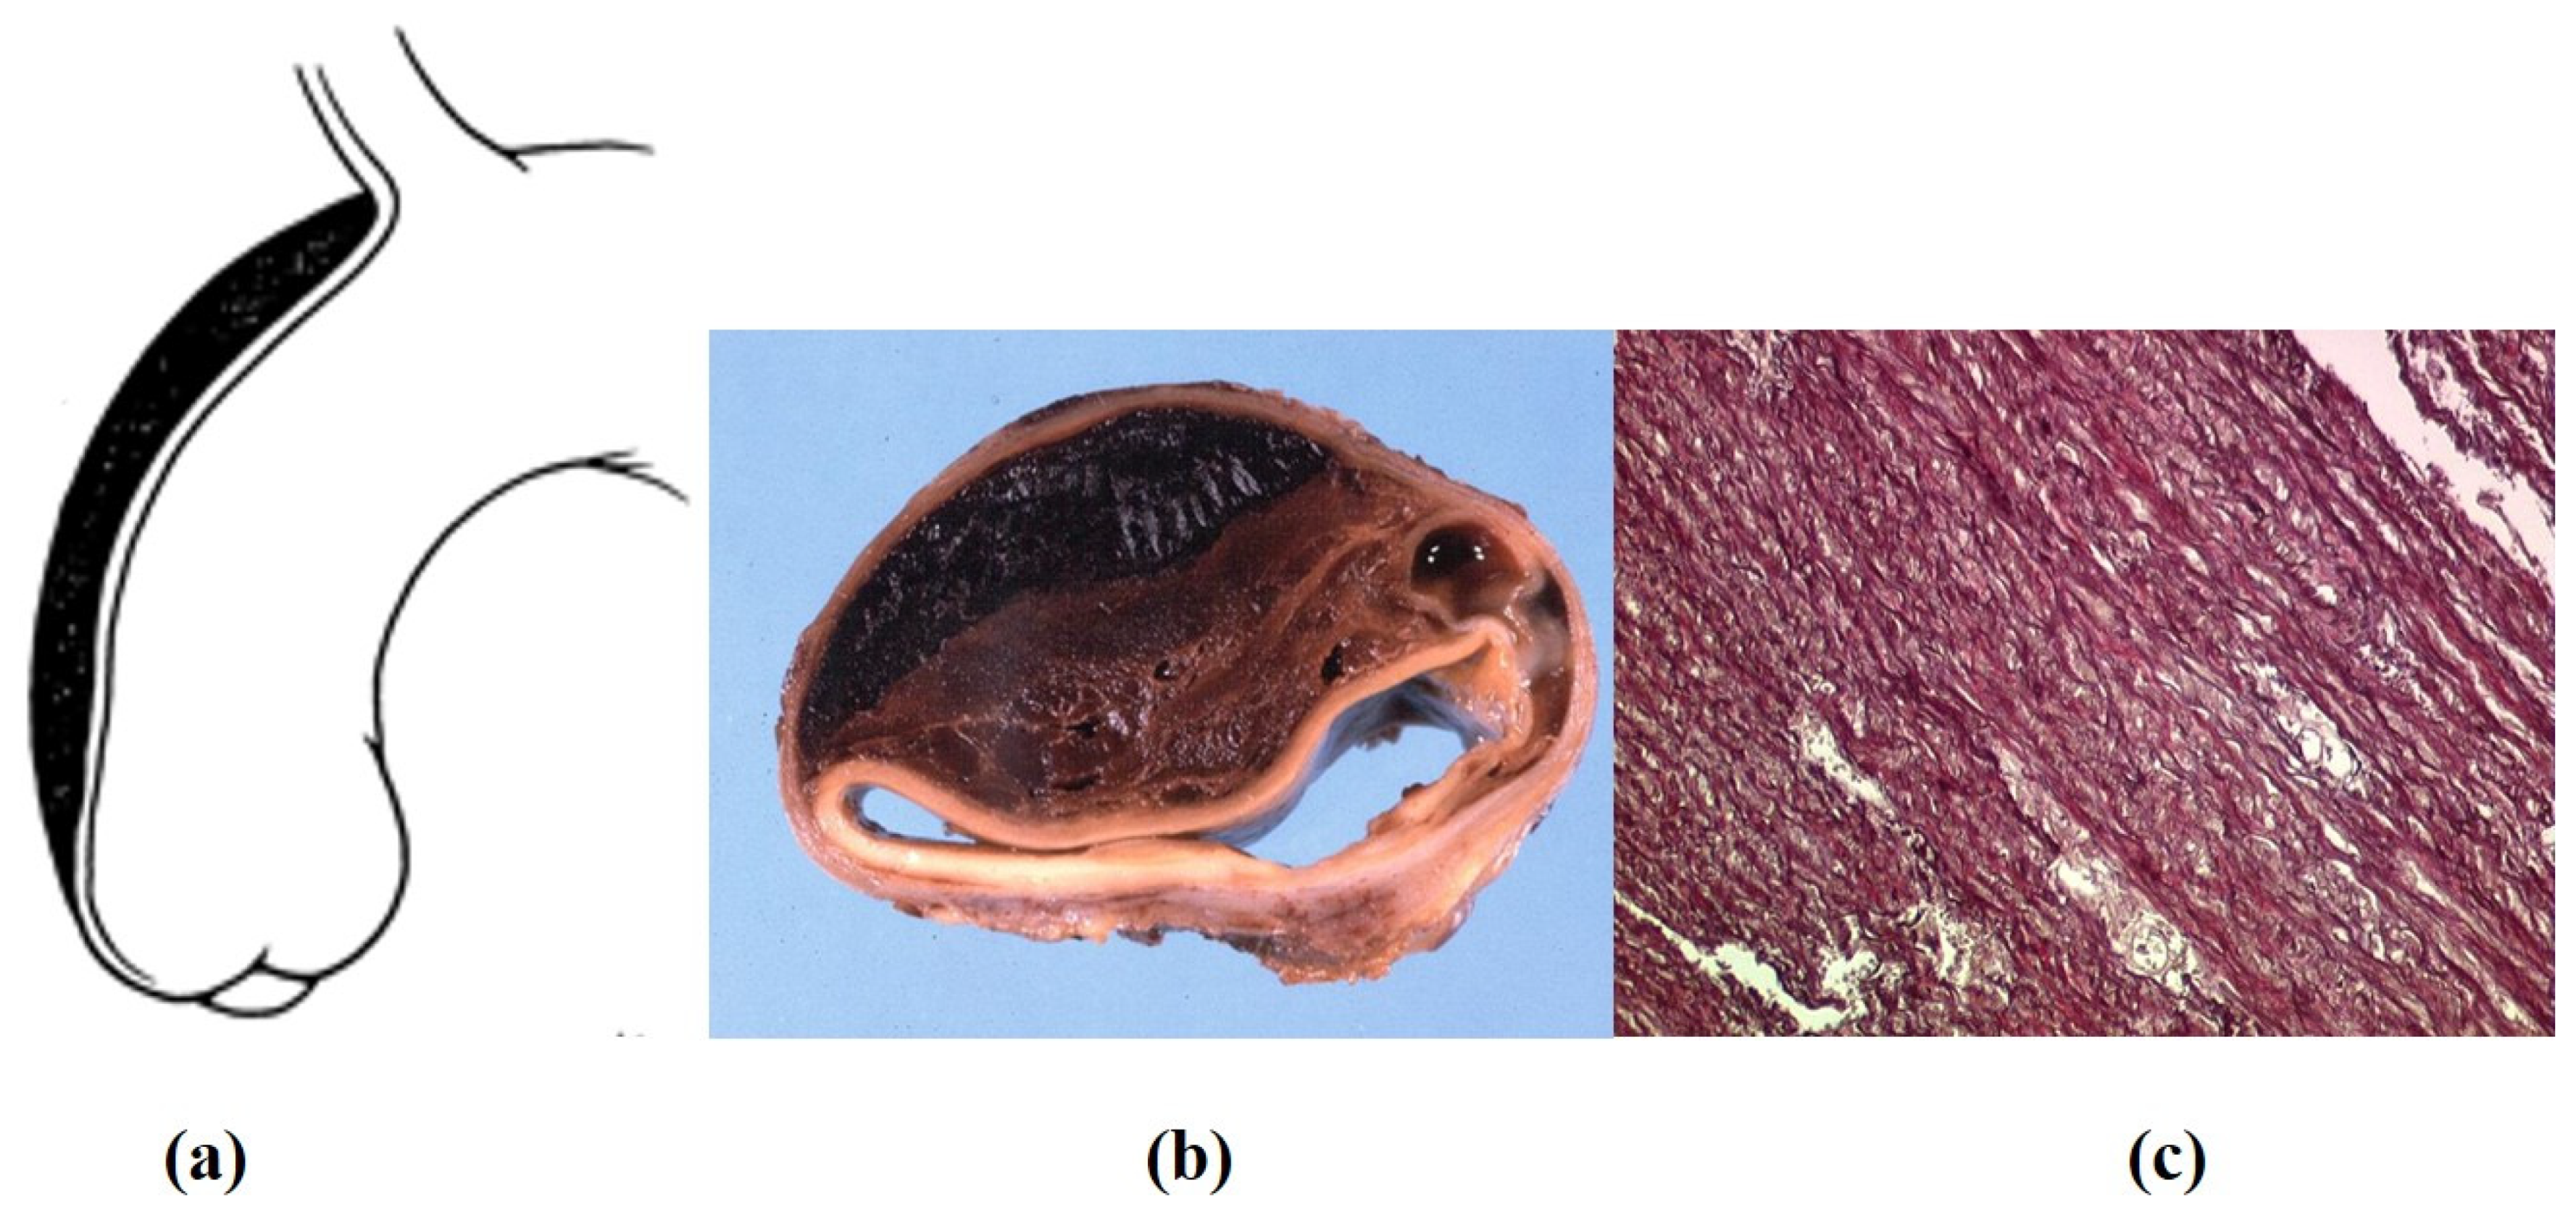

- Decellularization in unimplanted allografts appeared complete, both in the lamellar units of the tunica media and valvular interstitium with disappearance of endothelial lining (Figure 31);

- Cellular repopulation was observed in the outer part of implanted homograft wall by novel smooth muscle cells in the lamellar units (Figure 32a,b) and in the intima with a novel myointimal layer; this layer was noticed also in small animals such as rodents [68]. Novel endothelial cells appeared to line both the aortic wall intima and inflow/outflow at the cusp surface, as well as vasa vasorum, and valve spongiosa appeared repopulated by interstitial cells (Figure 32c,d);

- The ultrastructure of the wall revealed that novel smooth muscle cells have immature aspects, with a central oval nucleus, few contractile filaments and focal densities mainly located close to cytoplasmic membrane and in the paranuclear region; repopulated cells of the cusps are scarcely differentiated cells, in some case showing short intercellular junctions, rough endoplasmic reticulum and focal basal lamina (Figure 33), whereas others exhibited a fibroblast-like morphology;

- The undifferentiated nature of the repopulated cells is demonstrated by colocalization of some biomarkers. Novel wall cells showed positivity both for α-SMA and vimentin and novel cusp cells for SMA, vWF, VEGF, VEGF R2, α-SMA and CD57 (HNK-1), which is a neural crest marker;

- The origin of repopulated cells may be vasa vasorum for the homograft outer wall and the blood stream itself for cusps. Recently it has been demonstrated in a GFP rodent model that all novel cells belong to the recipient [68]. Bone marrow may be a source of progenitor cells (endothelial and mesenchymal cells) contributing to recruitment of smooth muscle-like cells [69,70]. Circulating bone-marrow-derived endogenous cells can be recruited in vivo by adhering to the intimal surface [71,72] and then recruited, undergoing an endothelial-to-mesenchymal transition (EMT) within the valve, followed by differentiation into interstitial cells that ultimately synthesize and remodel the ECM;

- Cell density, when compared to non-decellularized control allografts, showed 20% repopulation both in the aortic wall and at the cusp level (Figure 34);